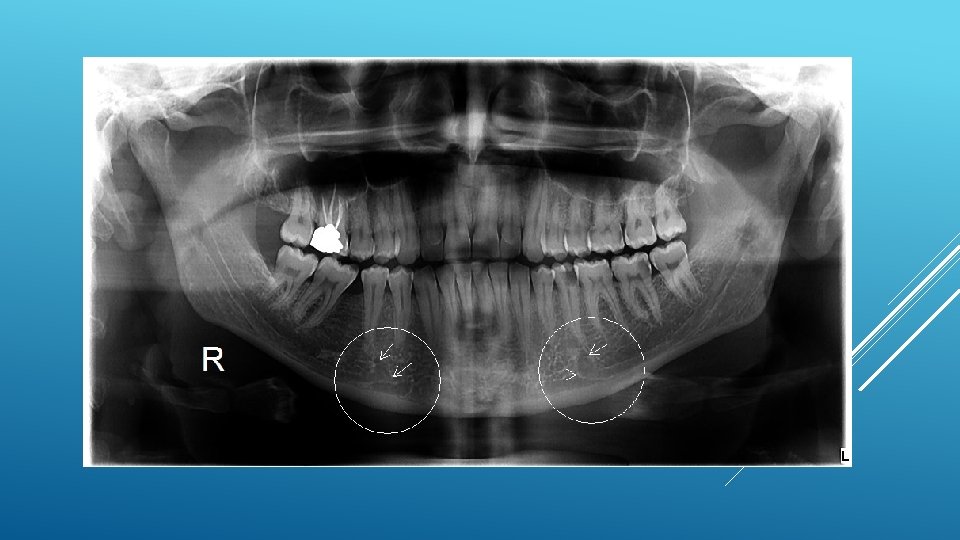

LOCATION AND DIMENSIONS OF THE MENTAL FORAMEN: A RADIOGRAPHIC ANALYSIS BY USING CONE-BEAM COMPUTED TOMOGRAPHY The majority of MF (56%) were located apically between the 2 premolars, and another 35. 7% of MF were positioned below the second premolar. On average, the MF was localized 5. 0 mm from the closest root of the adjacent tooth (range, 0. 3 -9. 8 mm). The mean size of the MF showed a height of 3. 0 mm and a length of 3. 2 mm; however, individual cases showed large differences in height (1. 8 -5. 1 mm) and in length (1. 8 -5. 5 mm). All mental canals exiting the MF demonstrated an upward course in the coronal plane, with 70. 1% of the mental canal presenting an anterior loop (AL) in the axial view. The mean extension of AL in cases with an AL was 2. 3 mm.

RELATIONSHIP BETWEEN THE POSITION OF THE MENTAL FORAMEN AND THE ANTERIOR LOOP OF THE INFERIOR ALVEOLAR NERVE AS DETERMINED BY CONE BEAM COMPUTED TOMOGRAPHY COMBINED WITH MIMICS The parameters were measured, and their values include mean (SD) anterior loop length, 1. 16 (1. 78) mm; anterior loop angle, 19. 13 (26. 89) degrees; inferior alveolar canal diameter, 3. 01 (0. 67) mm; height of the inferior alveolar canal, 10. 32 (1. 56) mm; 2 -dimensional mental foramen diameter, 2. 97 (0. 61) mm; 3 D mental foramen diameter, 2. 95 (0. 59) mm; 2 -dimensional vertical height of the mental foramen, 14. 67 (1. 67) mm; and 3 D vertical height of the mental foramen, 14. 61 (1. 69) mm. The mental foramen was located apically between the first and second premolars in 51. 67% and below the second premolar in 40. 83% of the cases.

THE MENTAL FORAMEN OR "THE CROSSROADS OF THE MANDIBLE. " AN ANATOMIC AND CLINICAL OBSERVATION] [ARTICLE IN FRENCH, GERMAN] THOMAS VON ARX 1 This paper presents a clinical and anatomical review of the mental foramen (MF) based on recent publications (since 1990). Usually, the MF is located below the 2 nd premolar or between the two premolars, but it may also be positioned below the 1 st premolar or below the mesial root of the 1 st molar. At the level of the MF, lingual canals may join the mandibular canal (hence the term "crossroads"). Accessory MF are frequently described in the literature with large ethnic variations in incidence. The emergence pattern of the mental canal usually has an upward and posterior direction. The presence and extent of an "anterior loop" of the mental canal may be overestimated with panoramic radiography. Limited cone-beam computed tomography currently appears to be the most precise radiographic technique for assessment of the "anterior loop". The mental nerve exiting the MF usually has three to four branches for innervation of the soft tissues of the chin, lower lip, facial gingiva and mucosa in the anterior mandible. The clinician is advised to observe a safety distance when performing incisions and osteotomies in the vicinity of the MF.

ANATOMICAL RELATIONSHIP BETWEEN MENTAL FORAMEN, MANDIBULAR TEETH AND RISK OF NERVE INJURY WITH ENDODONTIC TREATMENT he root apex of the mandibular second premolar (70 %), followed by the first premolar (18 %) and then the first molar (12 %), was the closest to the MF. Ninetysix percent of root apices evaluated were >3 mm from the MF. An AL was present in 88 % of the cases. Conclusions: With regards to endodontic treatment, the risk of nerve injury in the vicinity of the MF would appear to be low. However, the high incidence of the AL highlights the need for clinicians to be aware and careful of this important anatomical feature.

ASSESSMENT OF MORPHOLOGICAL AND ANATOMICAL CHARACTERISTICS OF MENTAL FORAMEN USING CONE BEAM COMPUTED TOMOGRAPHY All mental foramina were visualized. Regarding location, 49. 2% of the MFs were located between first and second premolars, 7. 7 distal and 39. 7% coincident to the apex of the mandibular second premolar. The mean MF opening angle was 45. 4° on the right side, and 45. 9° on the left. There were no statistically differences between gender groups with regard to the opening angle degree